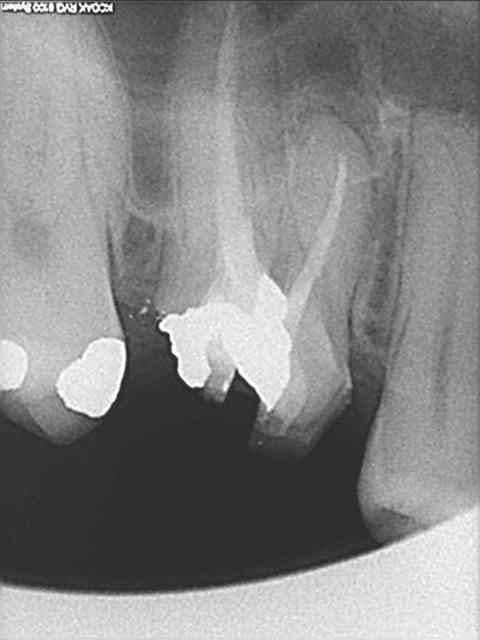

je sais pas si c'est un produit miracle, mais pour les sinus lift, c'est fantastique.

outre le fait de stabiliser un implant dans un sinus type SA4, pas de risque de voir partir le produit comme avec les granules de bioos et autres..

quasiment 6 mois entre les deux interventions (sinus lift et mise à jour)

c'est surtout la qualité des trabéculations osseuses qui m'interpelle.

d'habitude, on voit toujours un peu de particules, ici, c'est vraiment top.

je crois que c'est la première fois que je vois une cliché radio à quelques mois post-op avec ce matériau et le résultat semble excellent.